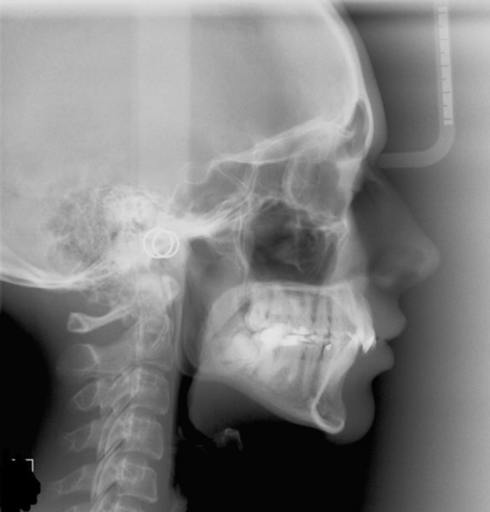

I'm 16, currently wearing braces on and faced this issue. So I'm here to ask whether I should go for it or not? Here's the situation, as you can in the picture on the last 2nd counting from the right(below), the tooth is not straight up. My dentist recommended me to upright my tooth by going through surgery and extract my last last tooth out then putting a screw in it and make a sectional braces to upright the unstraight tooth. I really doesn't want to spend my parent's money cause the braces is already very costly. They told me to go for it, but I can see in their eyes that some burden has added to them :( and also I felt uncomfortable, imagine drilling a screw in your jaws...ouch! What should i do? Should I go for it or not? Isit worth it for that one single tooth? My dentist said if I din't go through this process, I would face tooth decay in a high risk.